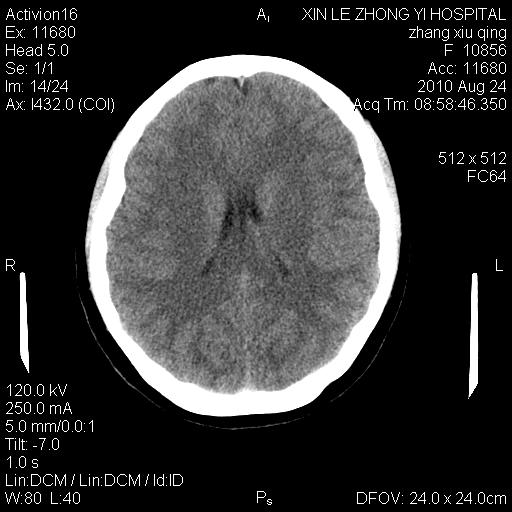

标题: CT28569:看看鞍上池正常吗

女 24 偶有头晕

未见明显异常,必要时可作mri

没什么!只是扫描层面与听眦线不平行

伪影干扰下,所见无水肿、无占位,建议定期复查。